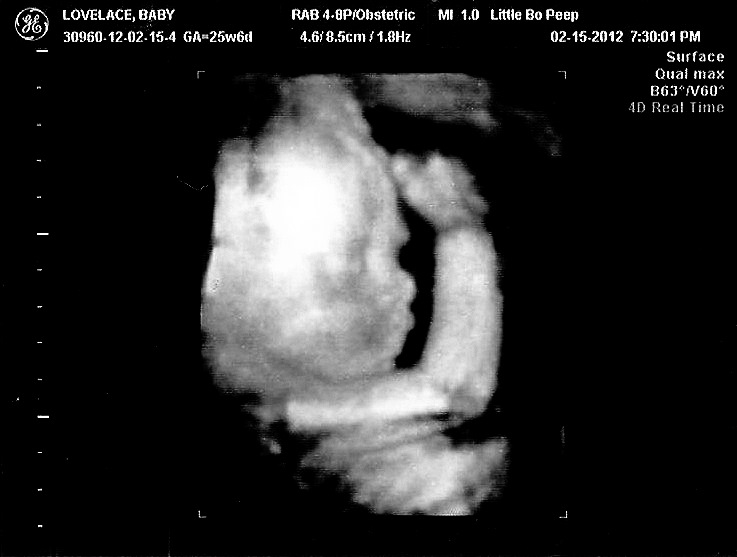

We spent the rest of the week getting our celebration on, in anticipation of getting another sneak peak at Baby Boy Lovelace! We did ye olde "Wednesday Night Special" at our local 3D joint ($70.00 for 20 minutes of fun, a ringing endorsement!) as a gift to ourselves. Or maybe I was obsessed and decided we should go. It's amazing to see how much he has grown!

Check him out, in all his glory!

| Get a load of this cutie! |

I am very strong #Team Lovelace with this kiddo's profile...Glenn's family has a prominent brow-bone and HUGE beautiful eyes, and I think the forehead/eye area is all Glenn.

Even the directly "face on" shot I am seeing Lovelace in the forehead/eyes and bridge of nose area...he may have a bit of me in his nose and lips and chin shape.

I know ultrasounds (even the 3d versions) are creepy as all get-out, and I am the first to admit they all can look pretty damn similar...but it is fun to try to discern features from each side of the family. Having a hard time seeing much of "me" in these photos - but love that he's looking like his papa!

So yes, it was totally worth it to get these images and see Mr. Baby Man dancing around and showing off on screen. The ultrasound tech this go round was leaps and bounds better than the last and really took her time AND more photos than she really had to. No complaints here!